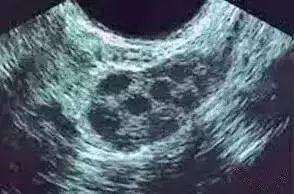

在生育治疗期间往往会跟踪卵泡的生长和发育,通过超声检查计数,也称为窦卵泡计数(AFC),可作为生育力测试的一部分,该测试可以评估卵巢储备。

当卵泡发育为具有卵泡腔的阶段被称为窦卵泡。它们的直径在2到10毫米之间。在超声波上最终可以看到窦卵泡。

窦卵泡计数是一种生育测试,这是通过经阴道超声波完成的,一般是在周期第2天和第5天的之间,超声技术将查看每个卵巢并计算2到10毫米之间的卵泡数量。

- 次级卵泡,也称为窦卵泡(这是一个包含充满液体腔的卵泡,此阶段的卵泡通过经阴道超声可见)